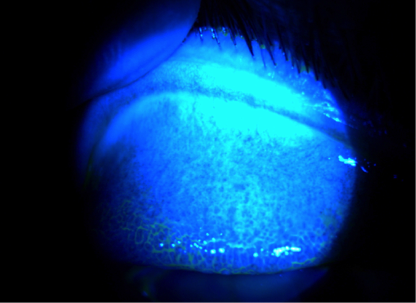

Puntos en la parte blanca del ojo

Los puntos en el blanco del ojo pueden ocurrir por diferentes razones. Preste atención al color y tamaño de los puntos.

- Un punto de color rojo brillante suele ser una hemorragia subconjuntival. Esto es un vaso sanguíneo roto que puede parecer aterrador, pero normalmente es inofensivo y se mejora por sí solo.

- Un punto de color gris puede ser un indicador de una condición benigna, pero debe ser revisado por un oftalmólogo. A veces, puede ser un signo de deficiencia de hierro o anemia.

Un punto de color café suele ser un nevus o una peca en el ojo, similar a las que podemos tener en la piel. Ocurre con más frecuencia en personas con cabello u ojos oscuros, porque naturalmente producen más melanina. Un nevo por sí solo no indica un problema, pero un oftalmólogo debe controlarlo a lo largo del tiempo para detectar cambios en su color o su tamaño.

Si aparece una mancha después de una lesión en el ojo, visite al oftalmólogo de inmediato.